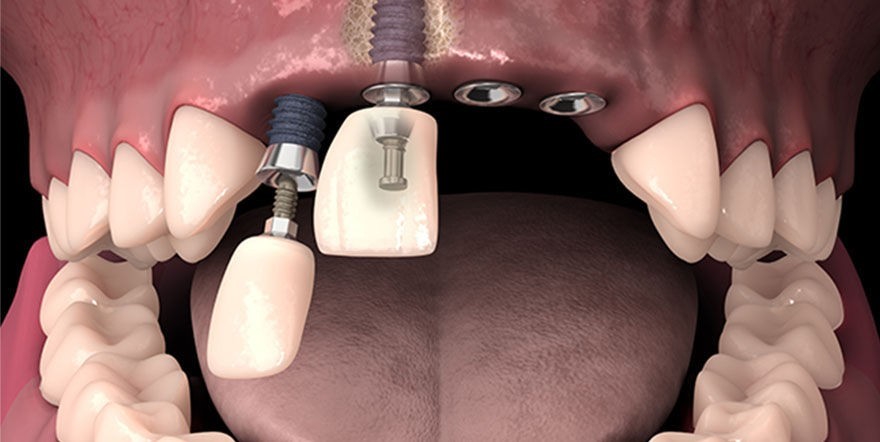

Интересует тема имплантации, что ставили, как долго восстанавливались, что у вас с функцией ПОЖРАТ, что вам предлагали ставить, на что согласились.

Сделали мне цистэктомию с удалением зуба переднего (резца), консервативное лечение не помогло, попутно разъебали всю кость-десну и теперь огромный провал-долина на месте где зуб был. По КТ уже было видно огромную площадь кисты и сразу сказали что костную пластику надо делать, хотели сразу после удаления но хирург разрезав сказала что киста рыхлая и хуевая и не будет делать пластику т.к. высок риск отторжения материала.

Пока что зашила меня и отправила отдыхать, через неделю осмотр, примерно через месяц сказала можно подумать будет над пластикой.

Алсо подскажите мне, нужно ли мне с имплантологом сразу до костной пластики знакомится-работать показаться или пластикой задача челюстно-лицевого хирурга заниматься, а к импантологу уже после месяца через 6 после пластики?